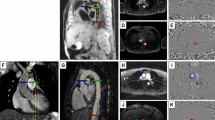

Phase contrast MRI

Phase contrast MRI acquisitions were specifically designed to acquire time-velocity curves at two slices locations (aortic arch and descending aorta approximately 10 cm apart) to estimate transit time (ΔT) as shown in Fig. 1. Subjects were scanned using a Philips Achieva 3 Tesla scanner and a six channel cardiac coil was employed for signal reception. Phase contrast MRI data was acquired by experienced radiographers using a high temporal resolution sequence (repetition time / echo time / flip angle / number of excitations / slice thickness = 5 ms/2.9 ms/100/1/8 mm, SENSE factor 2, field of view 300 mm × 225 mm, reconstructed voxel size 1.17 mm2, velocity encoding = 150 m/s, 44 phases, breath hold duration ~19 s) at both slice locations which were the aortic arch (AAo) and the descending (DAo) aorta (Fig. 1). Additional scout images were acquired to facilitate positioning of the phase contrast MR acquisitions and to ensure that the slices were positioned perpendicular to aorta at both locations. Q-flow analysis package (Philips, Viewform) was employed to extract time-velocity curves as shown in Fig. 1 and to estimate precise distance (ΔX) between the two slice locations. The time-velocity curves were then used to determine transit time (ΔT) and compute MR pulse wave velocity = ΔX/ΔT using an in house Matlab based program. A reproducibility analysis of this technique was performed in seven normal volunteers, repeating scans at two sessions, and within each session performing the scanning twice. For session one the values were 4.9 ± 1.6 and 4.5 ± 1.6 m/s (mean difference 0.4 ± 0.9) and session two 5.5 ± 1.6 and 5.2 ± 1.2 m/s (mean difference 0.3 ± 0.7).

Illustration of Vicorder and phase contrast MRI techniques. In panel a, examples of simultaneous Vicorder carotid and femoral arterial waveforms are shown. Panel b shows the two slices of thoracic aorta (AAo – aortic arch, and DAo descending aorta) between which distance is measured (ΔX), and in panel c phase contrast MRI flow images showing ΔT which is the time delay between of the initial upstroke in flow between the two slices